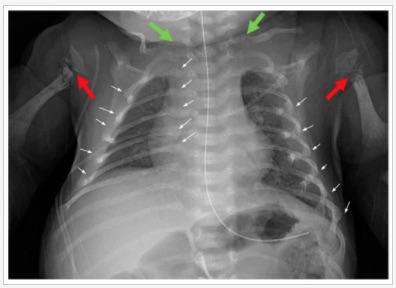

The article is a case report from the Ehlers-Danlos Clinical Research Program at the Boston University Medical Campus, where researchers examined ultrasounds of the developing fetus at several points during gestation and identified what looked like fractures suffered in utero. X-rays after birth confirmed the findings. The boy tested negative for osteogenesis imperfecta (OI) and other known causes of fragile bones, including vitamin D deficiency. The authors note: